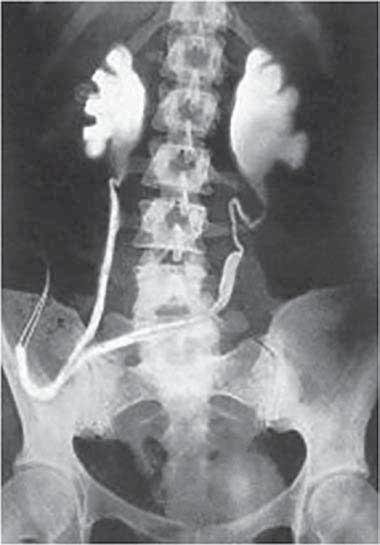

Rycina 87.4. ileal conduit a, ).